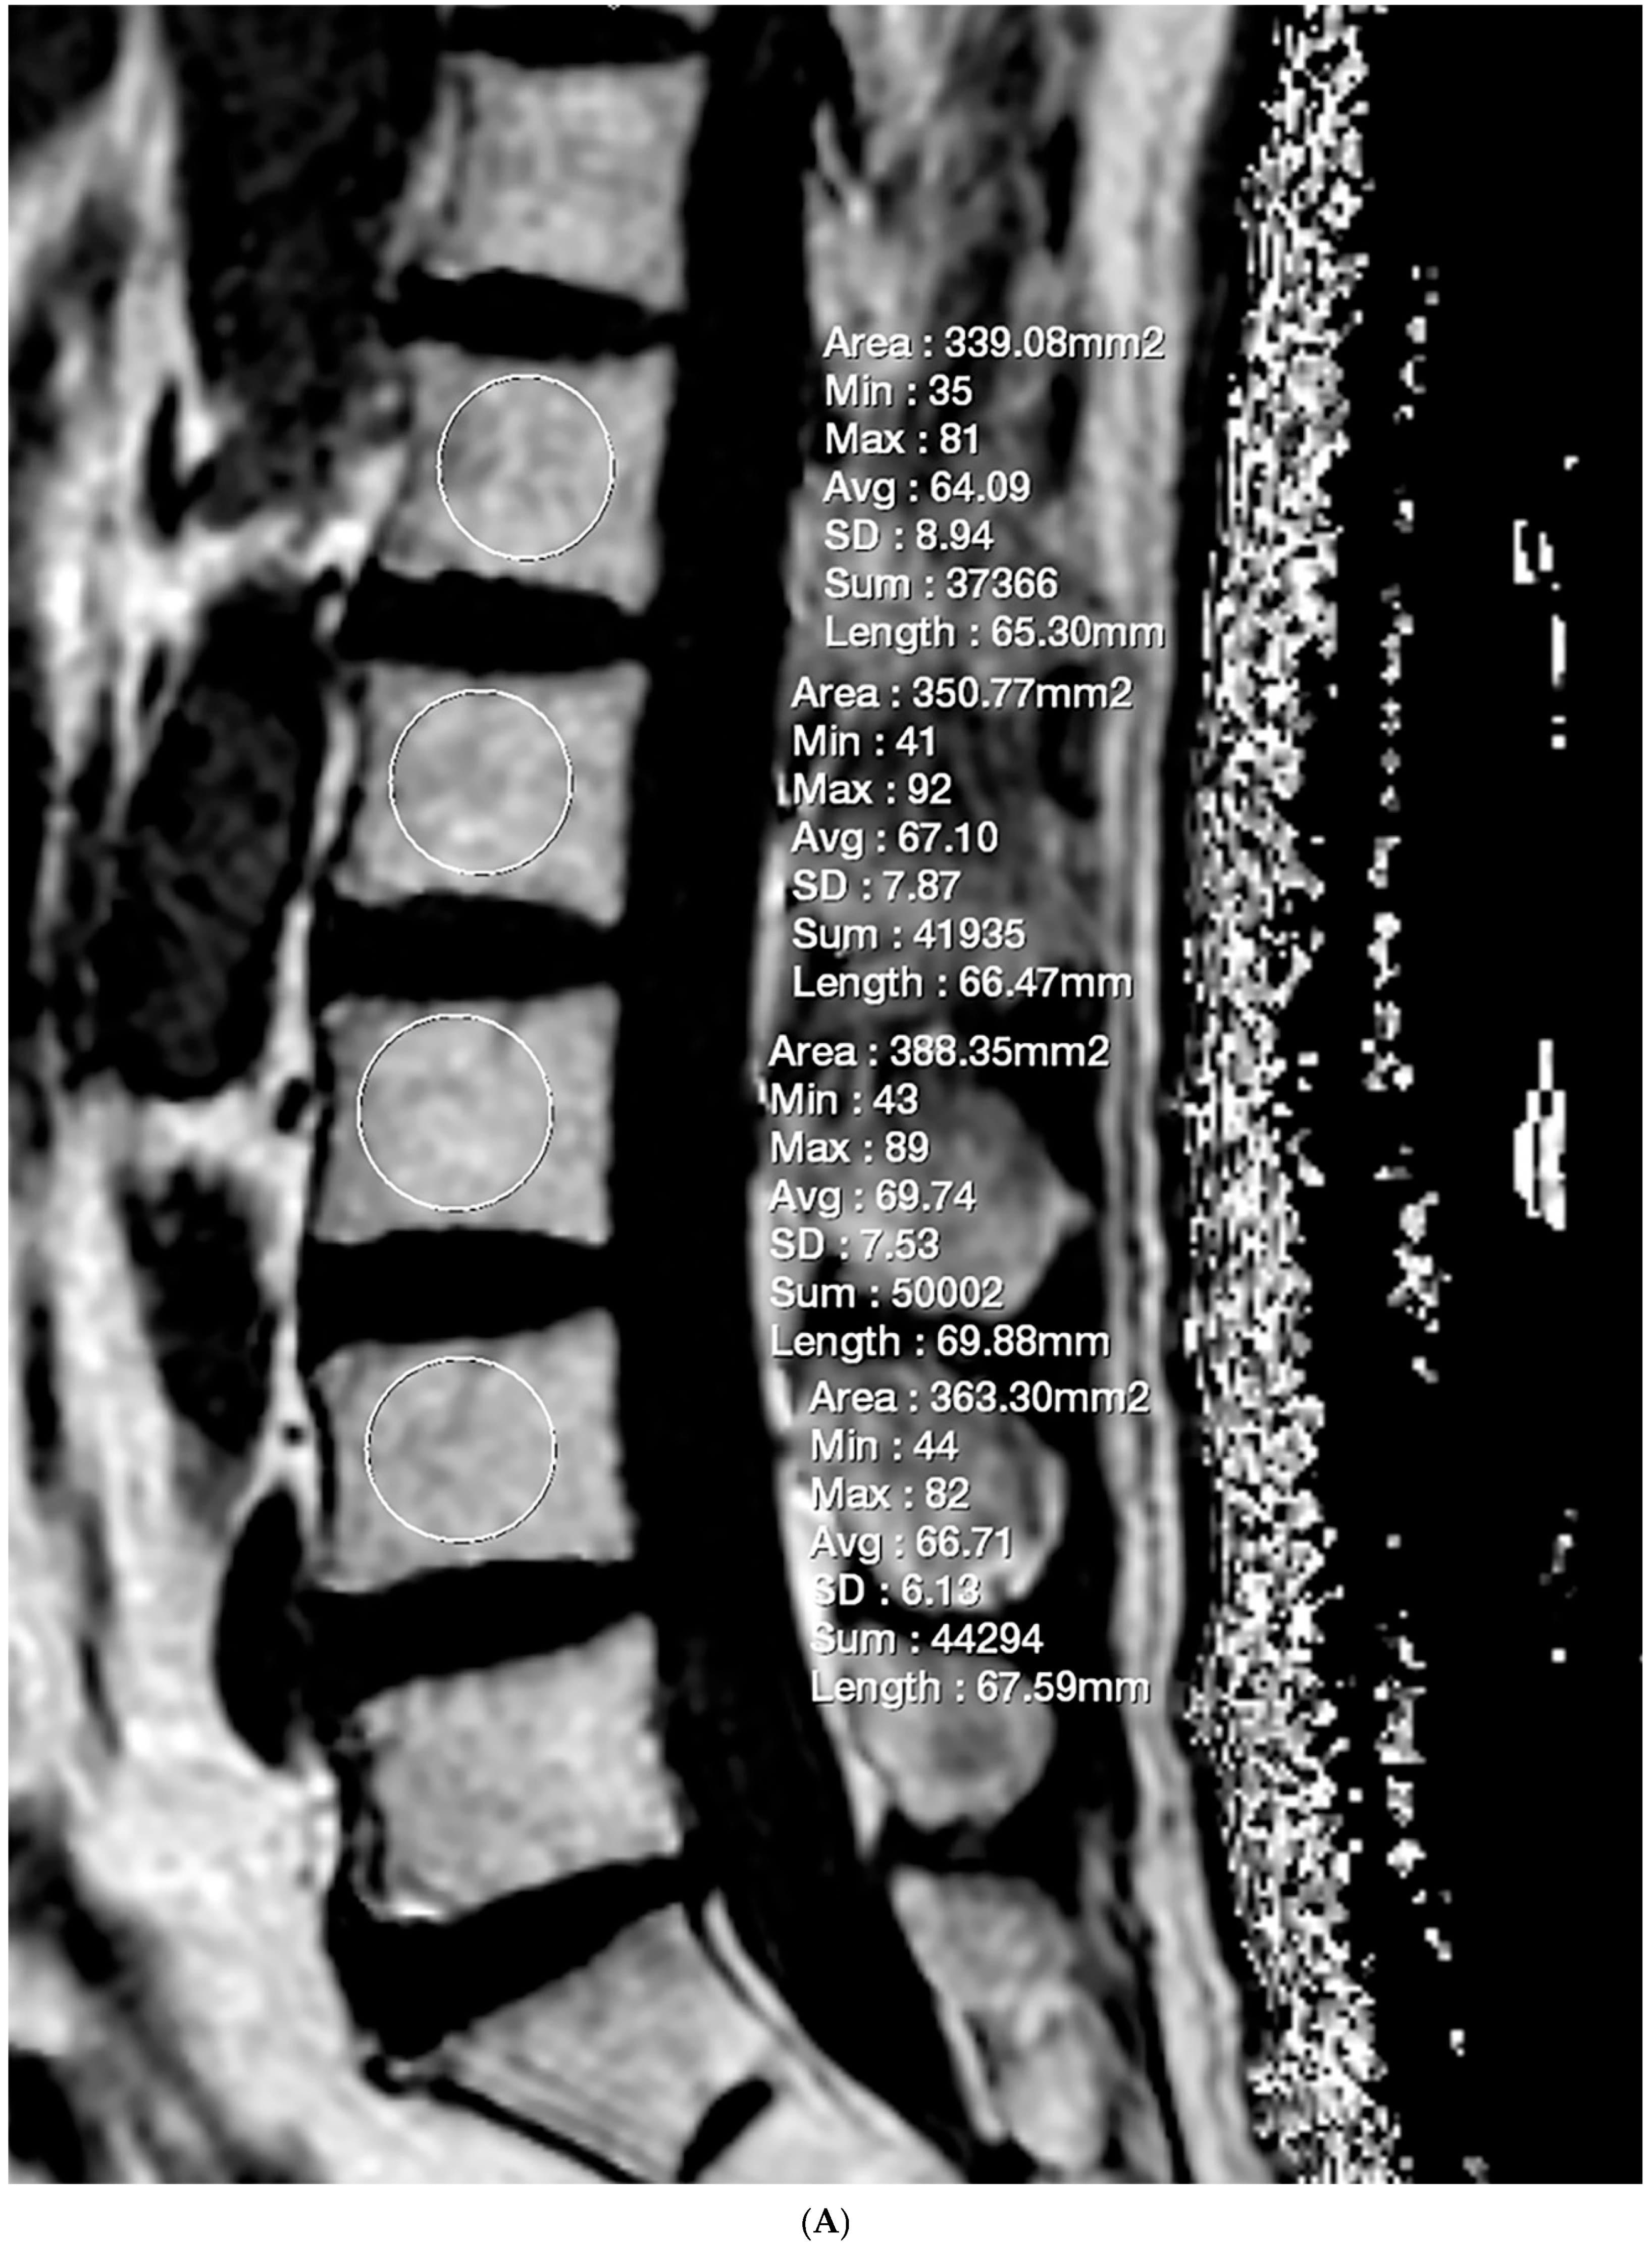

2.3. Fat Fraction Measurement